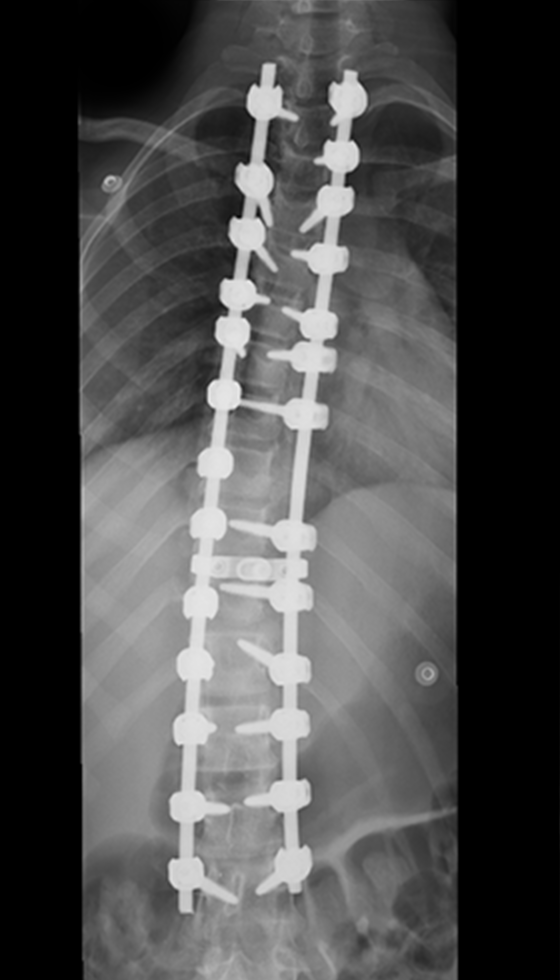

Gallery : Before - After